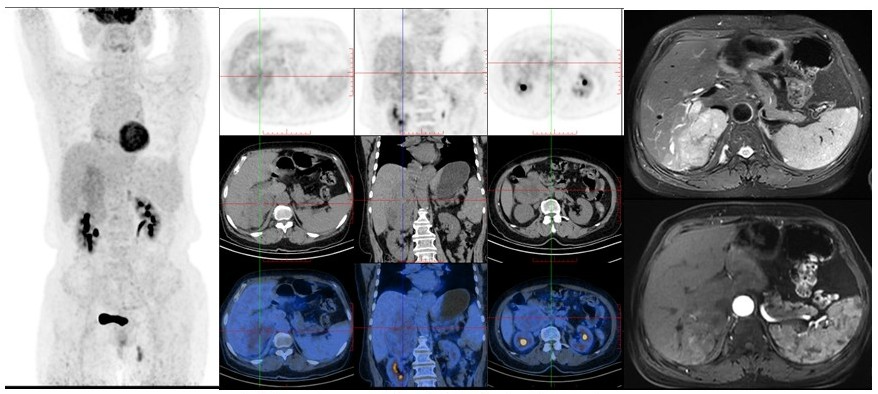

病例(4为一中年女性,因体检发现右肾上腺肿物就诊,实验室检查提示贫血MRI检查示右侧肾上腺区巨大占位伴出血囊变,呈T1WI稍低信号、压脂T2WI稍高信号、DWI不均匀高信号改变18F-FDG PET/CT示占位实性成分代谢不均匀增高,腹膜后淋巴结代谢未见明显增高;(腹膜后肿物)切除病理为神经鞘瘤。

4. 女,41岁,体检发现右侧肾上腺区肿物神经鞘瘤